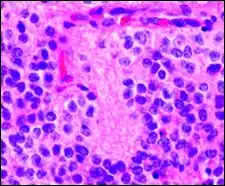

Периваскулярные псевдорозетки в эпиндимоме

Эпендимальные псевдорозетки вокруг пролиферирующего эндотелия при анапластической эпендимоме